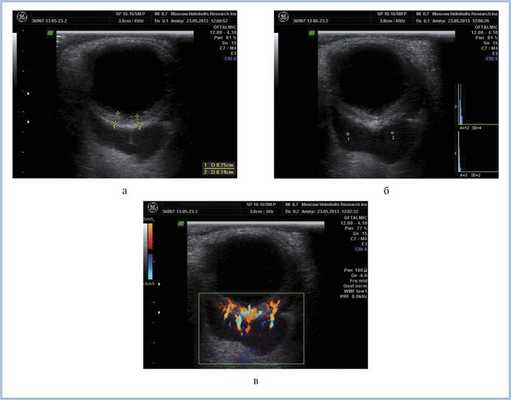

Ультразвуковое исследование глазных яблок в режиме «general» и «vitreous»: OD - в стекловидном теле участок повышения эхо-сигнала, сетчатка прилежит. OS - тотальная отслойка сетчатки с утолщением оболочек глаза. Инфильтрация стекловидного тела отсутствует (рис. 5). Рисунок 5. Рис. 5. В-сканы глазных яблок в витреальном режиме: небольшой участок повышения эхо-сигнала в стекловидном теле правого глаза (а); субатрофия глазного яблока, отслойка сетчатки, утолщение оболочек левого глаза (б).

КТ позволила выявить ретробульбарную ткань с достаточно четкими границами, локализующуюся вокруг зрительного нерва, а также утолщение хориоидеи слева (рис. 4). Патологических изменений справа по данным КТ выявлено не было. С помощью УЗДС слева в В-режиме непосредственно за задним полюсом глаза (вокруг зрительного нерва) определяли гипоэхогенную, практически однородную опухолевую ткань с четкими неровными контурами. Одновременно выявили диффузное утолщение хориоидального слоя в области заднего полюса глаза — до 2,5 мм (рис. 5, а). Ультразвуковой денситометрический анализ, проведенный на основе двумерных серошкальных гистограмм, продемонстрировал крайне низкие значения акустической плотности ткани (А=3—12 усл. ед.) (см. рис. 5, б). В режиме цветового допплеровского картирования (ЦДК) отмечена гиперваскуляризация ретробульбарного и интраокулярных очагов с высокими линейными характеристиками кровотока. Следует отметить, что два указанных процесса — внутриглазной и орбитальный имели единую васкуляризацию (см. рис. 5, в). Патологических изменений в правом глазу по данным ультразвукового исследования выявлено не было.

Рис. 5. Результаты дуплексного сканирования. а — утолщение хориоидеи; б — денситометрические показатели акустической плотности опухоли в В-режиме; в — множественные собственные сосуды опухоли, единая васкуляризация внутриглазного и орбитального очагов в режиме ЦДК.

Рис. 9. Дуплексное сканирование левого глаза и орбиты через 6 мес после ПХТ. Определяется уменьшение размеров опухолевой ткани в В-режиме (а), сохранность собственной васкуляризации в режиме ЦДК (б).